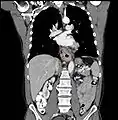

Esophageal cancer (lower part) as a result of Barrettʼs esophagus

Additional testing is needed to assess how much the cancer has spread (see § Staging, below). Computed tomography (CT) of the chest, abdomen and pelvis can evaluate whether the cancer has spread to adjacent tissues or distant organs (especially liver and lymph nodes). The sensitivity of a CT scan is limited by its ability to detect masses (e.g. enlarged lymph nodes or involved organs) generally larger than 1 cm.[41][42] Positron emission tomography is also used to estimate the extent of the disease and is regarded as more precise than CT alone.[43] Esophageal endoscopic ultrasound can provide staging information regarding the level of tumor invasion, and possible spread to regional lymph nodes.